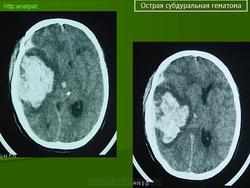

Субдуральные гематомы представляют собой кровоизлияние между твердой мозговой оболочкой и паутинной оболочкой, непосредственно покрывающей мозг, и обычно происходят вследствие разрыва сосуда на поверхности мозга. В большинстве случаев Субдуральные гематомы располагаются на обширной территории над лобными и теменными долями. Острые субдуральные гематомы - это кровоизлияния, произошедшие в сроки до 72 часов и выглядящие на КТ головного мозга как гиперденсивные образования. Подострые субдуральные гематомы это кровоизлияния от 3 до 20 дней, которые на КТ выглядят как изоденсные или гиподенсные относительно головного мозга образования. Хронические Субдуральные гематомы - это гематомы старше 21 дня (3 недель), которые выглядят, как гиподенсные образования на КТ. Тем не менее, Субдуральные гематомы могут быть смешанными, например, когда происходит острое кровоизлияние в полость хронической гематомы. Острые субдуральные гематомы встречаются у 5-25% пациентов с тяжелой черепно-мозговой травмой. Хронические субдуральные гематомы насчитывают 1-5.3 на 100 000 населения в год. Более свежие исследования демонстрируют более высокую частоту гематом в связи с улучшением техники нейровизуализации. В противоположность эпидуральным гематомам, которые обычно не распространяются за пределы костных швов черепа, субдуральные гематомы могут быть очень протяженными по площади, распространяясь от серпа мозга до намета мозжечка. Острые субдуральные гематомы вследствие травмы наиболее опасные из всех повреждений мозга, сопровождающиеся наибольшей летальностью, если вовремя не провести хирургическое вмешательство.

Острая субдуральная гематома.

Острые субдуральные гематомы - это кровоизлияния, произошедшие в сроки до 72 часов и выглядящие на КТ головного мозга как гиперденсивные образования. Подострые субдуральные гематомы это кровоизлияния от 3 до 20 дней, которые на КТ выглядят как изоденсные или гиподенсные относительно головного мозга образования. Хронические Субдуральные гематомы - это гематомы старше 21 дня (3 недель), которые выглядят, как гиподенсные образования на КТ. Тем не менее, Субдуральные гематомы могут быть смешанными, например, когда происходит острое кровоизлияние в полость хронической гематомы. Острые субдуральные гематомы встречаются у 5-25% пациентов с тяжелой черепно-мозговой травмой. Хронические субдуральные гематомы насчитывают 1-5.3 на 100 000 населения в год. Более свежие исследования демонстрируют более высокую частоту гематом в связи с улучшением техники нейровизуализации.